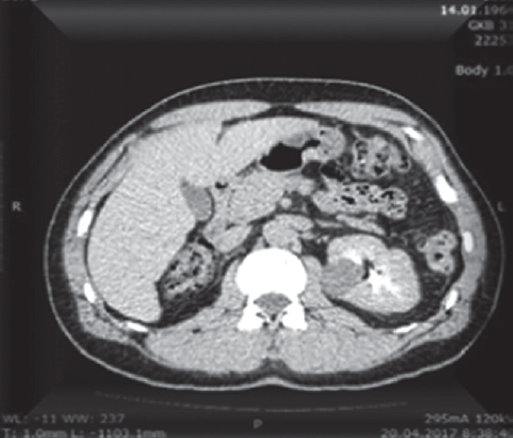

В данном сообщении описано клиническое наблюдение больного М., 53 года, оперированного по поводу опухоли единственной левой почки. Правая почка была удалена вследствие гидронефротической трансформации 32 года назад. В дальнейшем пациент находился под наблюдением амбулаторных уролога и нефролога, признаков снижения суммарной почечной функции не отмечалось. В апреле 2017 г. при плановом УЗИ выявлено образование верхней трети единственной левой почки. С целью уточнения диагноза была выполнена МСКТ, при которой было подтверждено наличие внутриорганного образования верхней трети левой почки размером 3,0 × 2,9 × 2,3 см, прилежащего к чашечно-лоханочной системе (рис. 1). По данным МСКТ и остеосцинтиграфии поражение регионарных лимфатических узлов и отдаленные метастазы отсутствовали.

Рис. 1. МСКТ с внутривенным контрастированием больного М. Визуализируется опухоль единственной левой почки, прилегающая к чашечно-лоханочной системе

Fig. 1. Multislice spiral computed tomography with intravenous contrasting of the patient. A tumor of the solitary left kidney is shown adjacent to the pelvicalyceal system